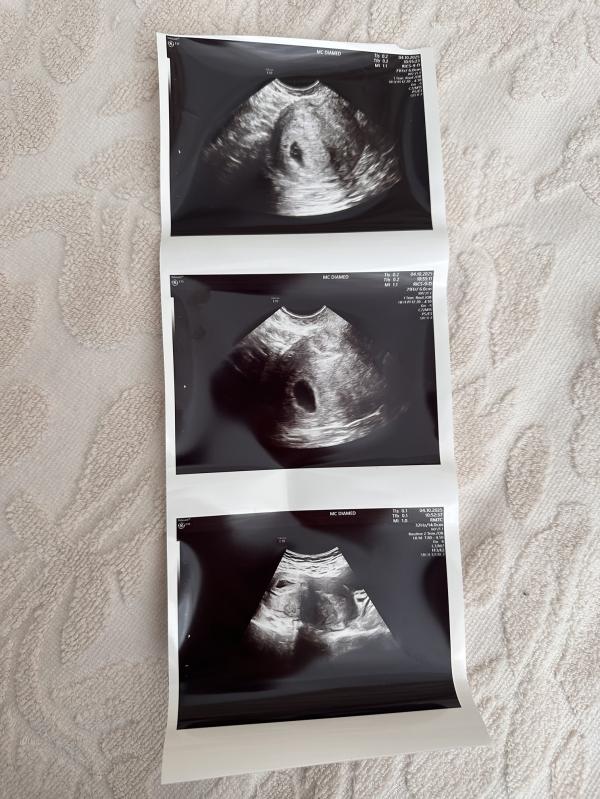

Сегодня делали узи , плодное яйцо уже в матке 🥹 только я не совсем поняла эмбрион есть или нет , сказали через неделю повторить узи